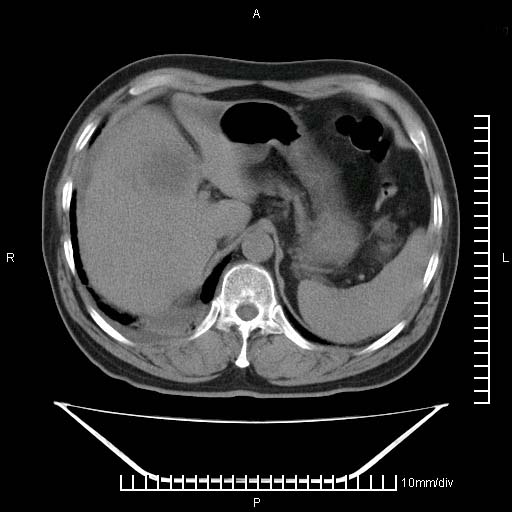

标题: CT25082:肝脏增强:男性,70岁 [打印本页]

标题: CT25082:肝脏增强:男性,70岁

患者以心脏疾病收住院,腹部无明显症状,b超查肝脏有占位。

增强效果不理想。考虑转移,胆囊壁明显增厚,不排除胆囊癌肝转移。

病灶无强化,考虑囊肿。

牛眼征,中心坏死无强化,外缘强化,最外缘又见低密度,考虑转移,与脓肿鉴别

肝内多发转移瘤,右下肺炎症并少量胸水。胃壁增厚建议胃镜,胰尾部“病变”为肠管。

1)肝脏多发性转移瘤(不排除胰尾癌转移所致可能)。2)腹水。3)右侧少量胸腔积液。

ct25082 结果:转移瘤

外院mr结果:胰尾恶性占位。